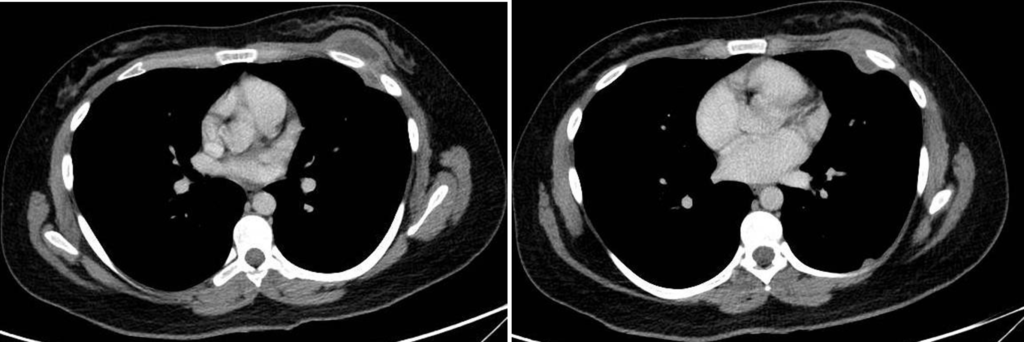

Paciente femenina de 26 años de edad, sin antecedentes patológicos de relevancia, sin dosis de vacuna BCG. Cursa con cuadro clínico de ocho meses de evolución, caracterizado por dolor en región pectoral izquierda intermitente, que se exacerba a la inspiración profunda. En el último mes se palpa masa indurada dolorosa a la palpación a nivel del cuadrante inferior interno de mama izquierda, motivo por el cual se realiza ecografía de partes blandas, donde se observa a nivel retropectoral en íntimo contacto con la parrilla costal imagen hipoecogénica de bordes delimitados, avascular al Doppler color por lo cual se solicita TC de tórax con EV. En ella se observa en topografía del cuarto espacio intercostal, imagen hipodensa con realce periférico tras la administración del contraste que desplaza por efecto de masa el parénquima pulmonar adyacente y se proyecta a la pared torácica anterolateral izquierda; mide 40 mm x 55 mm. Además, se visualiza otra imagen de similares características de base pleural en contacto con el octavo arco costal posterior izquierdo que mide 6 mm x 11 mm.

Cuatro meses posteriores a la PAAF la paciente refiere persistencia de dolor y aumento de tamaño de la masa asociado a eritema en región mamaria, por lo cual se realiza TC de tórax con contraste EV donde se observa imagen hipodensa ya conocida, con realce periférico tras la administración de contraste, con aumento de tamaño y bordes lobulados.